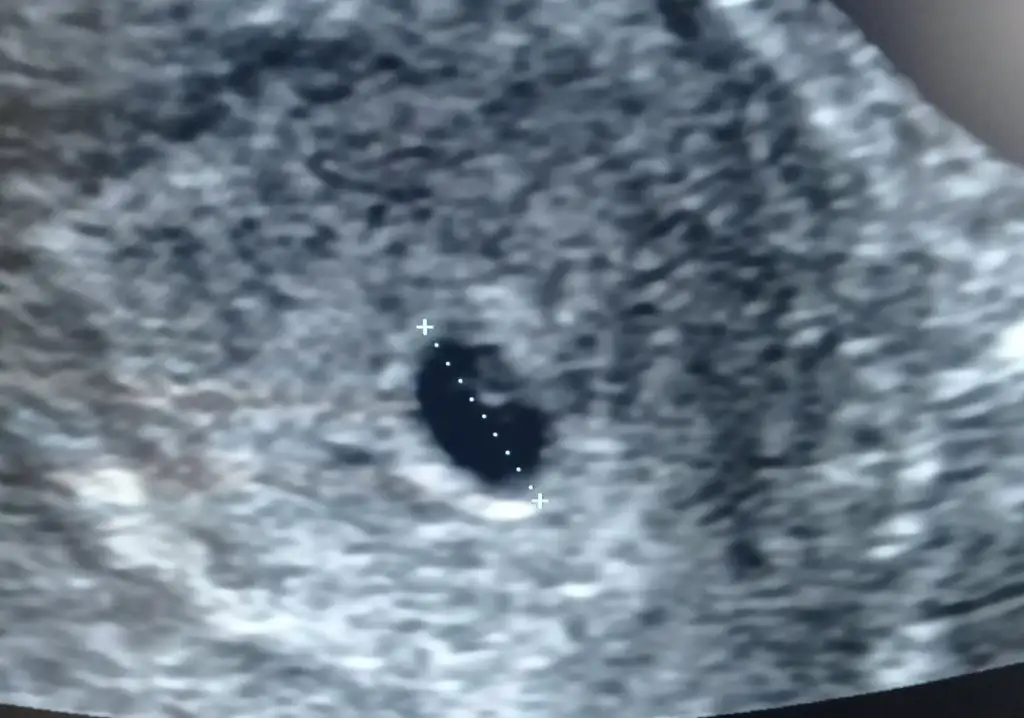

Ben de pıhtılaşma için her gün iğne yapıyprum kendime, korkmayın dua edin Allah’ın izniyle sağlıkla devam ederKızlar ben doktordan çıktım ilaç iyne falam yazdı. Moralim çok bozuk . Karnıma iyne vuracaklar 10haziran yine gidicem kalp atışı için gebelik çok stressli bişey korku insanı sarıyor. Doktorum bana ne aglama ne yüksekten gülme dedi. Ağır kaldirma yolculuk olmaz dedi